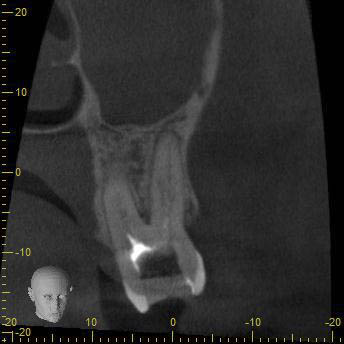

BN2627_DVT (6 von 17) Veröffentlicht 1. Dezember 2014 am 344 × 344 in Unerwartete Anatomie Zahn 26, 27- die WF